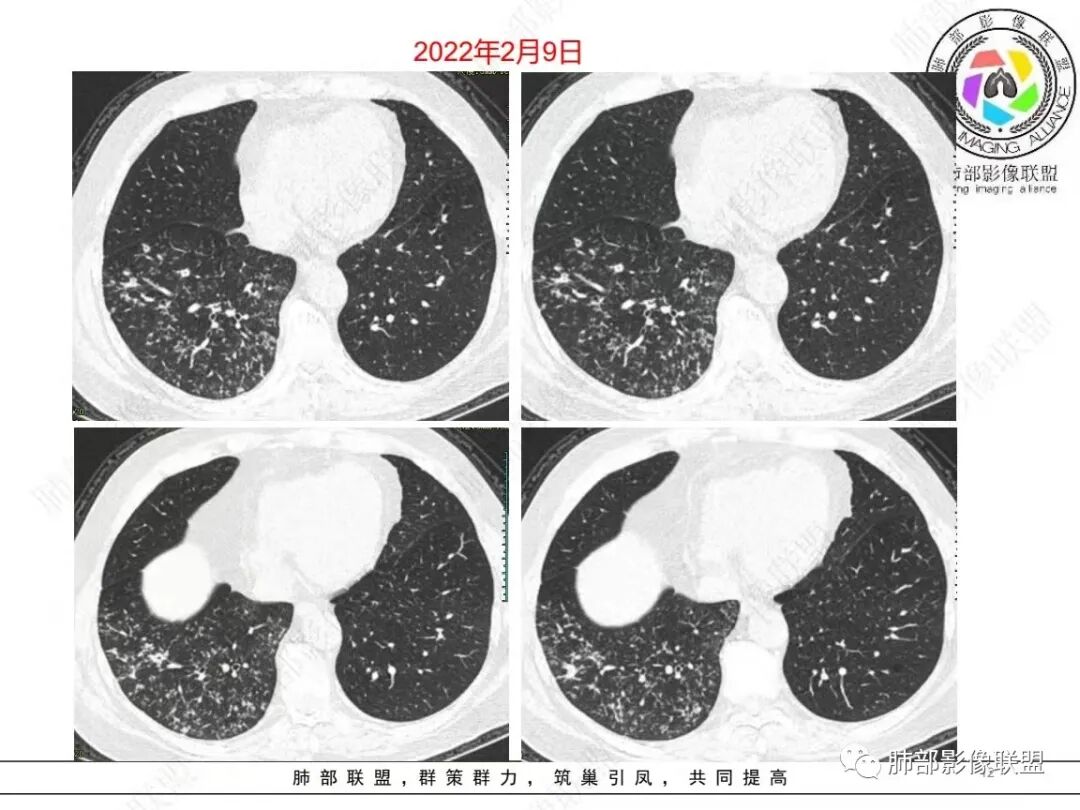

右肺下叶多发腺泡结节影,边缘部分模糊,伴树芽征,支气管壁增厚,10天复查腺泡结节有吸收变淡,病变内出现多发囊状影,考虑感染性病变,金葡?真菌?

中年男性,咳嗽咳黄脓痰一周,有糖尿病,肾病病史,长期使用激素血象白细胞自然会升高,但CRP明显升高。降钙素原不高,肺泡灌洗液阴性。右下肺沿支气管分布腺泡结节影,少于树芽征,小实变影,支气管壁轻度增厚,考虑感染性疾病,从病灶形态来看气道来源,复查病灶有小空洞形成,病灶明显吸收。考虑气道金葡菌肺炎,鉴别奴卡菌

中老年 男性 白细胞高,基础病多, 右肺下叶多发小结节 小斑片影,边缘模糊,伴树芽征,支气管壁略增厚,短期治疗后复查病灶有所吸收,可见小囊状透光区形成,考虑气道来源化脓性感染,金葡 可能

中老年男性,糖尿病史,免疫抑制,白细胞及C反应蛋白明显升高,右肺下叶多发腺泡结节、树芽,边缘模糊,支气管管壁增厚,治疗10日复查吸收好转,可见小空洞,考虑金葡,鉴别曲霉

就是病灶因为炎性反应,渗出、增生,会融合。

小树芽——增大,与旁边的病灶融合,形成大病灶。再融合——再增大。金葡菌发展速度快,很快就是一个大病灶,呈叶段性改变。

我们大部分都是在发病一两天之后看病,办手续,住院,做检查,这时候,金葡菌肺炎已经发展壮大了——大叶性改变了或者说大片了